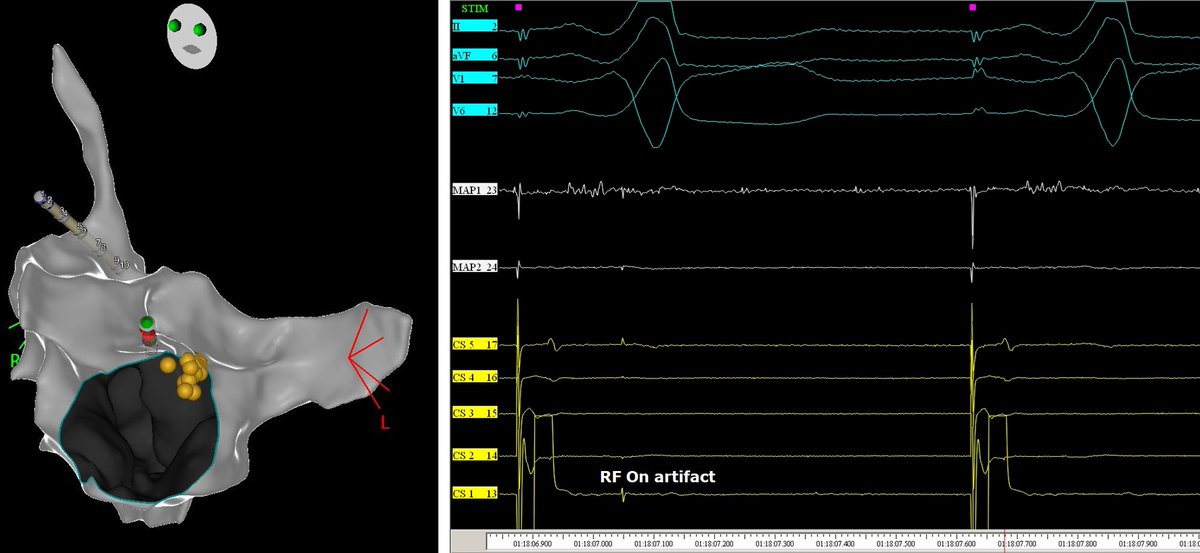

This pt with atypical AFL had a prior surgical abl at the time of MV repair. The CS d->p EGMs suggested a lateral LA source, but 3D activation had RPV carina in the circuit…which was the abl site! #mapmoreburnless @JoshSellke @maddyferraro1 @arcampado

FrischMd's tweet image. This pt with atypical AFL had a prior surgical abl at the time of MV repair. The CS d-&amp;gt;p EGMs suggested a lateral LA source, but 3D activation had RPV carina in the circuit…which was the abl site! #mapmoreburnless @JoshSellke @maddyferraro1 @arcampado